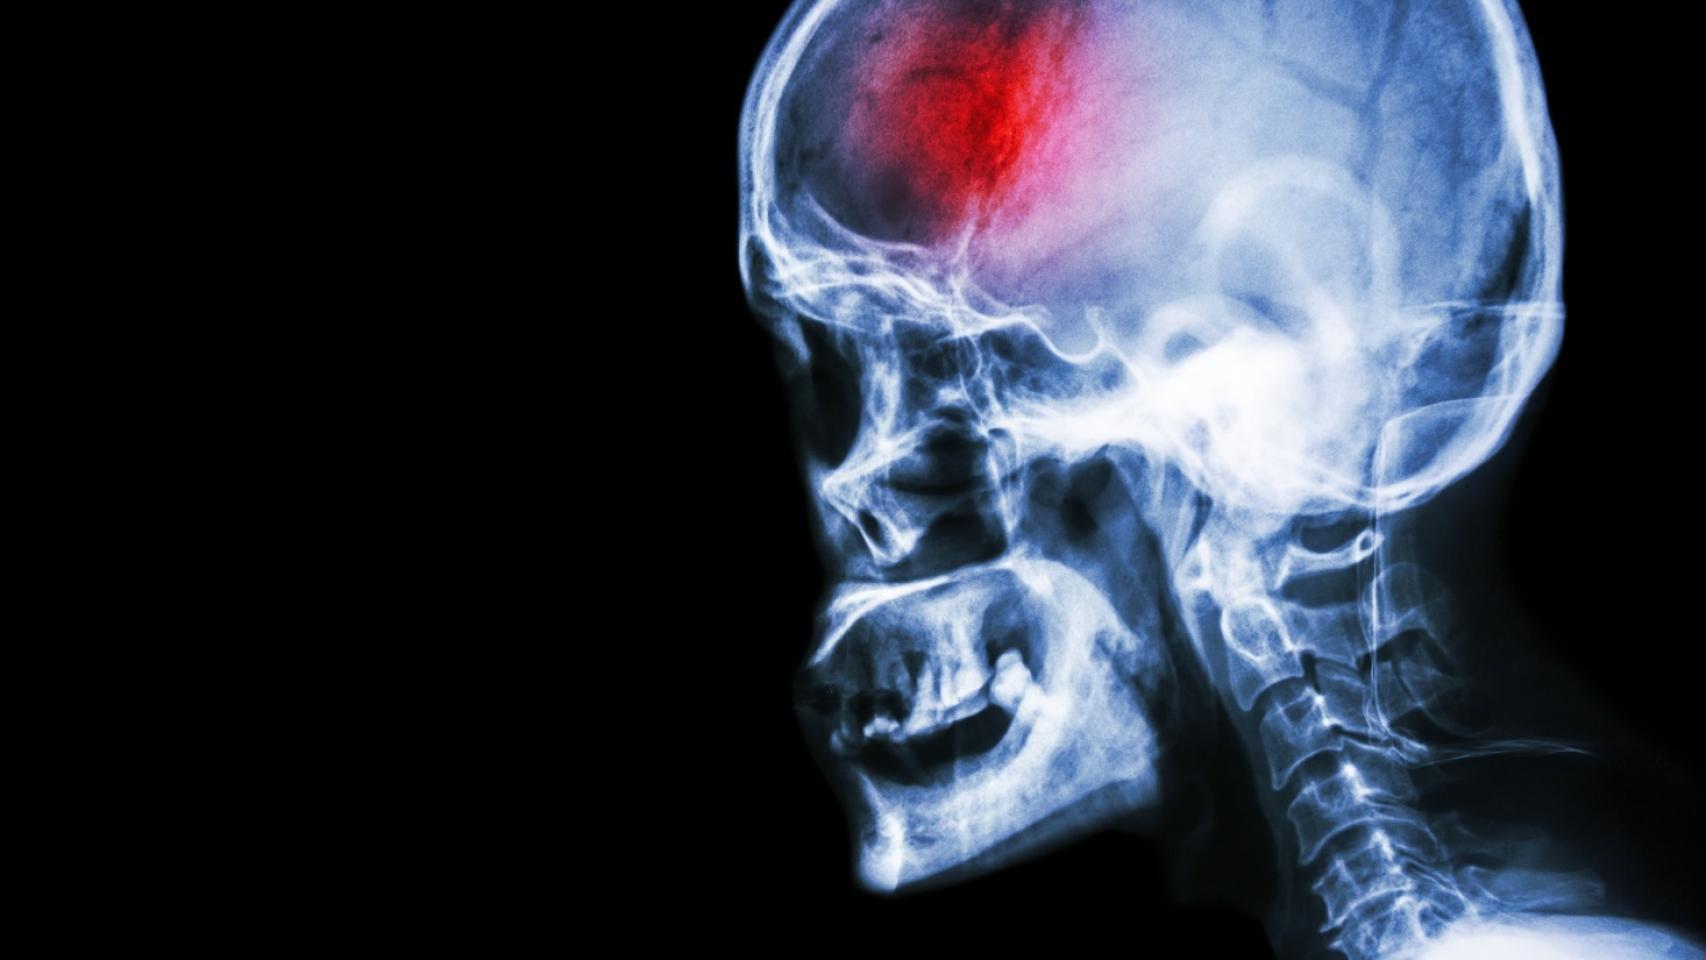

Cada año miles de personas ven cómo su vida cambia en cuestión de segundos tras sufrir un ictus. Muchos de ellos logran salvarse gracias a la rápida atención hospitalaria, pero una vez reciben el alta, empieza otra batalla: la rehabilitación.

A pesar de ser una de las principales causas de muerte en España, el ictus sigue siendo una enfermedad invisible, pero que cualquiera podría sufrir. Por ello, Burgos incide en que tener buenos hábitos saludables podría marcar la diferencia.

“El colesterol, el azúcar y la tensión son fundamentales de controlar y los picos de tensión te pueden dar un ictus directamente, ya que se producen por la obstrucción de una arteria”, explica, en relación a los factores de riesgo que se deben controlar para evitar un ictus.

En relación a los síntomas, sostiene que los más comunes son que la boca se caiga hacia un lado, perder el habla o la fuerza en algunas extremidades. “En ese momento hay que llamar a emergencias. Las primeras horas son cruciales”.